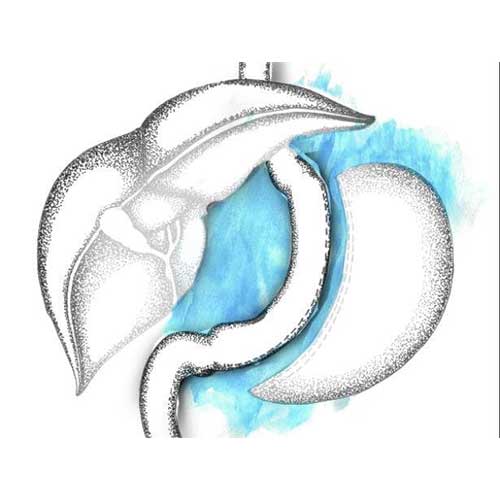

One of the most popular bariatric surgeries across the globe, the laparoscopic sleeve gastrectomy is an irreversible procedure that curtails the size of the stomach by surgically removing approximately two-thirds of it, making it roughly the size and shape of a banana. The procedure also eliminates most of the cells that produce ghrelin, the hunger-inducing hormone; thus, reducing your eating capacity post surgery and helping you lose weight quickly.

This procedure is the preferred choice for younger patients suffering from morbid obesity. It is helpful for patients suffering from various side-effects of obesity, such as diabetes, high blood pressure, sleep apnea, and PCOS. While the laparoscopic sleeve gastrectomy is a great first- stage procedure for patients falling under the super super obese (BMI more than 60-70) category, it is not recommended for patients suffering from severe gastroesophageal reflux disease or large hiatus hernia

Nearly 60 to 80 per cent of your excess body weight will reduce over a period of one-and-a-half years. You will observe rapid weight loss within the first three to four months post surgery, after which the rate of weight loss will slow down. You may also regain the lost weight due to overconsumption of high-calorie foods and liquids, and lack of regular physical exercise. However, you can avoid this, if you follow our exercise, nutrition and lifestyle tips, and maintain a proper follow-up routine.

The nerves of the stomach and the outlet valve (pylorus) are not altered, preserving the function of the stomach. The rest of the gastrointestinal tract anatomy is also not altered, so the food ingested follows the normal course. This results in a lesser chance of vitamin and mineral deficiencies and decreases the possibility of dumping syndrome.

This procedure is the preferred choice for younger patients suffering from morbid obesity. It is helpful for patients suffering from various side-effects of obesity, such as diabetes, high blood pressure, sleep apnea, and PCOS. While the laparoscopic sleeve gastrectomy is a great first- stage procedure for patients falling under the super super obese (BMI more than 60-70) category, it is not recommended for patients suffering from severe gastroesophageal reflux disease or large hiatus hernia.

Nearly 60 to 80 per cent of your excess body weight will reduce over a period of one-and-a-half years. You will observe rapid weight loss within the first three to four months post surgery, after which the rate of weight loss will slow down. You may also regain the lost weight due to overconsumption of high-calorie foods and liquids, and lack of regular physical exercise. However, you can avoid this, if you follow our exercise, nutrition and lifestyle tips, and maintain a proper follow-up routine.

The nerves of the stomach and the outlet valve (pylorus) are not altered, preserving the function of the stomach. The rest of the gastrointestinal tract anatomy is also not altered, so the food ingested follows the normal course. This results in a lesser chance of vitamin and mineral deficiencies and decreases the possibility of dumping syndrome.